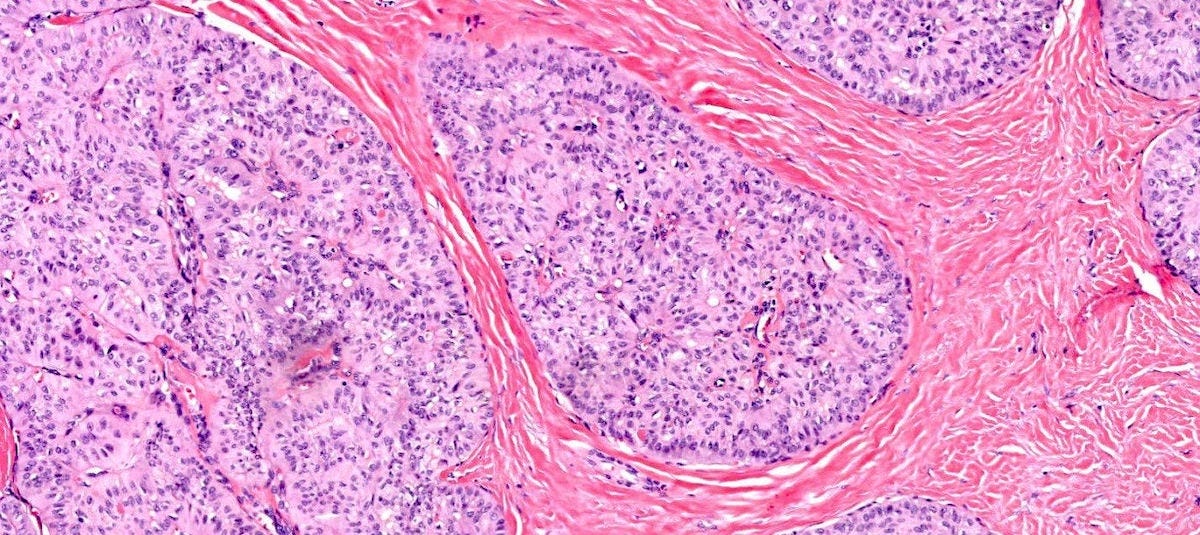

Medullary carcinoma of the breast is a rare subtype (3 - 5%) of invasive breast cancer with pushing borders, syncytial growth, high grade nuclei and a prominent lymphoid infiltrate. According to the World Health Organization, the preferred terminology is invasive breast carcinoma of no special type with medullary pattern.

Grossly, the tumors are usually 2 - 5 cm, well circumscribed, soft to firm, lobulated masses. Although they appear sharply demarcated from surrounding tissue, they lack a true capsule and may exhibit pushing, expansile borders without widespread stromal invasion.

Microscopically, medullary carcinoma is composed of large, pleomorphic, high grade tumor cells arranged in broad syncytial sheets occupying at least 75% of the tumor area. The tumor cells have vesicular nuclei (i.e., large, pale staining with a central clearing) with prominent nucleoli and abundant eosinophilic cytoplasm. A prominent and dense lymphoplasmacytic infiltrate surrounds and often infiltrates the tumor, suggesting a vigorous host immune response. Mitotic figures are numerous and areas of necrosis may be present.

Medullary carcinoma - radiologic and microscopic images